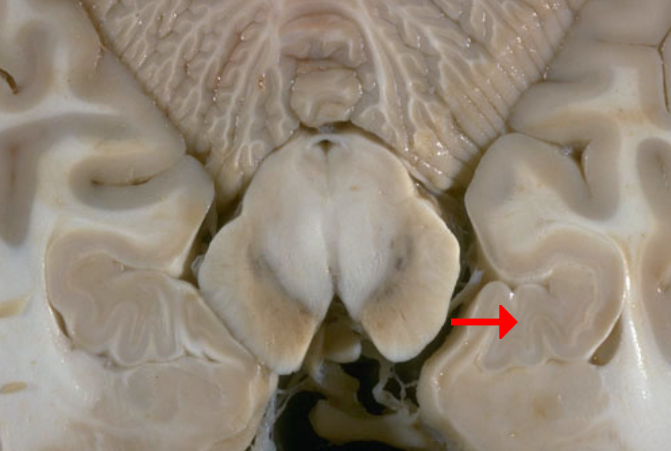

Name this brain structure

Temporal lobe

Label this brain part

Fornix

Label this brain structure

Caudate nucleus

Label this brain structure

Putamen

Label this brain structure

Globus pallidus

Label this brain structure

Amygdala